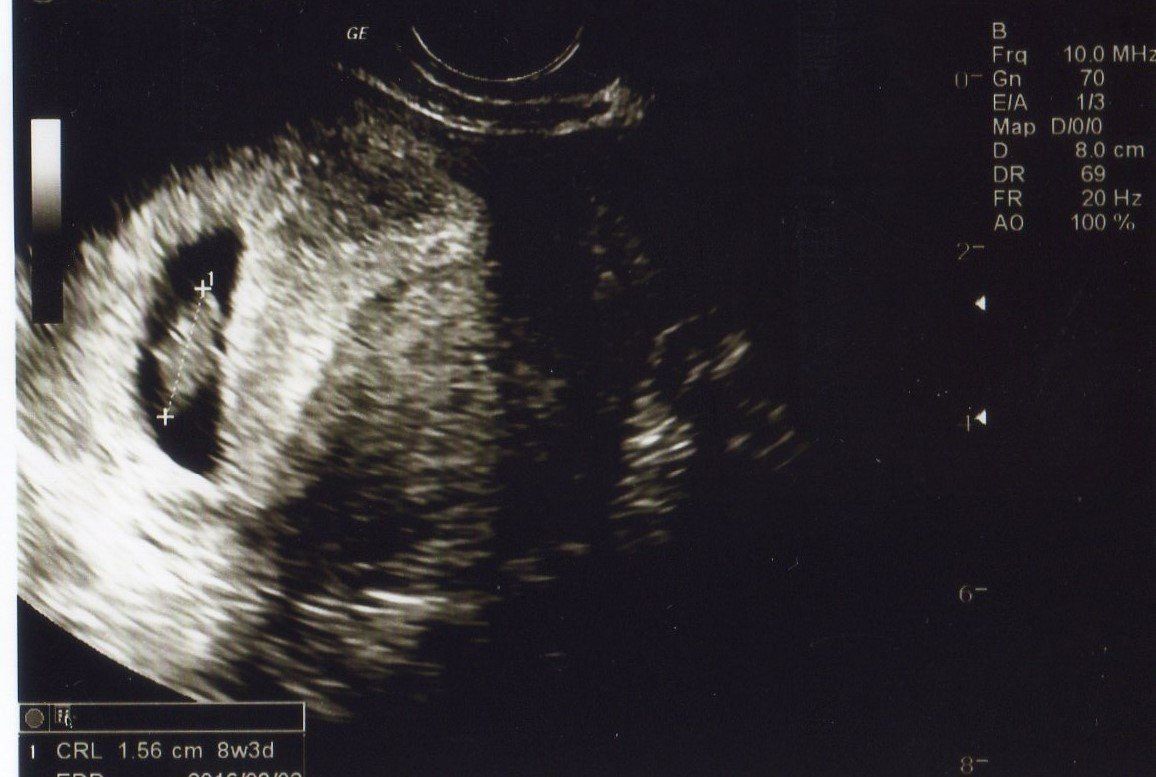

妊娠8週目 まめつぶのような姿の赤ちゃんにびっくり

写真左側の小さな黒色の袋(胎嚢)の中に赤ちゃんが見えます。私は初めて出会う赤ちゃんの姿に感動しました。赤ちゃんが、まめつぶのような姿だったので、「まめちゃん」と愛称で呼ぶようになりました。これから人間らしい姿へ変わっていく様子を見るのが、楽しみでしかたありませんでした。